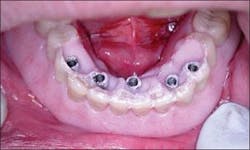

Figure 6 - Immediate placement of Nobel Replace Select fixtures after extraction of mandibular teeth

Figure 7 - Multiunit abutments placed and gingiva contoured and sutured

The surgical template was placed intraorally and utilized in implant placement, co-localizing the desired implant placement with the desired prosthesis (Figure 5). Five 4.3 mm x 13 mm Nobel Biocare Replace Select fixtures were placed in the anterior mandible immediately after extraction of the mandibular teeth (Figure 6). Minor autogenous bone grafting was utilized to repair minor bone defects.

Transmucosal multiunit abutments of appropriate tissue depth were selected and placed onto the implant fixtures and the soft tissue sutured, allowing for the platform of the abutments to be slightly coronal to the gingival margin (Figure 7).